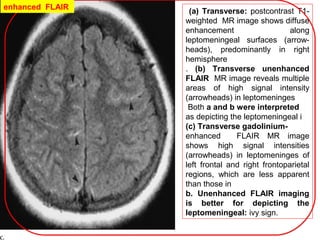

(a) Transverse: postcontrast T1-

weighted MR image shows diffuse

enhancement along

leptomeningeal surfaces (arrow-

heads), predominantly in right

hemisphere

. (b) Transverse unenhanced

FLAIR MR image reveals multiple

areas of high signal intensity

(arrowheads) in leptomeninges

Both a and b were interpreted

as depicting the leptomeningeal i

(c) Transverse gadolinium-

enhanced FLAIR MR image

shows high signal intensities

(arrowheads) in leptomeninges of

left frontal and right frontoparietal

regions, which are less apparent

than those in

b. Unenhanced FLAIR imaging

is better for depicting the

leptomeningeal: ivy sign.

enhanced FLAIR